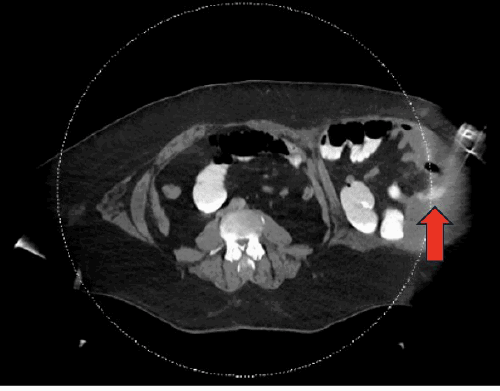

A 51-year-old morbidly obese male (body mass index [BMI] 47 kg/m²) with a remote history of laparoscopic cholecystectomy presented to the emergency department complaining of left-sided abdominal pain, nausea, and vomiting. An initial abdominal computed tomography (CT) scan revealed a large, left-sided lateral ventral hernia containing incarcerated bowel loops, consistent with a partial small bowel obstruction. Notably, due to the patient’s body habitus, the entirety of the hernia sac was not completely visualized on this initial study (Figure 1).

Figure 1. Initial CT Demonstrating Large Left Flank Hernia with Incomplete Visualization. Published with Permission

Axial view from the initial abdominal CT scan on presentation. The images demonstrate a large, left-sided lateral ventral hernia containing bowel loops. Note the incomplete visualization of the entire hernia sac due to the patient’s body habitus, with possible early fluid accumulation noted near the subcostal margin (arrow)

Coronal view from the initial abdominal CT scan on presentation. The images demonstrate a large, left-sided lateral ventral hernia containing bowel loops. Note the incomplete visualization of the entire hernia sac due to the patient’s body habitus, with possible early fluid accumulation noted near the subcostal margin